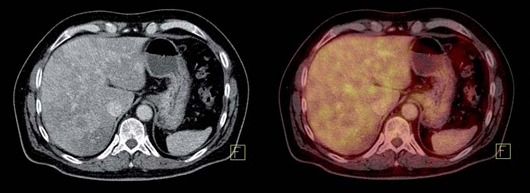

Tumores gastroenteropancreáticos

Este grupo (GEP) constituyen un grupo heterogéneo de tumores neuroendocrinos del estómago, páncreas e intestino. El más frecuente es el tumor carcinoide. El tratamiento primario es la cirugía aún en los pacientes con enfermedad metastásica, debido a que la resección parcial puede mejorar la calidad de vida, sobrevida y estado funcional. Las imágenes cumplen un papel importante para determinar la extensión de la enfermedad al inicio y en el seguimiento. Los estudios realizados con 111In pentatreotide muestran elevada sensibilidad para la detección de GEP a excepción del insulinoma. La sensibilidad para el gastrinoma metastásico, carcinoide y otros GEP son generalmente sobre 80% hasta 94%. La sensibilidad para la enfermedad metastásica tiende a ser superior a la de los tumores primarios (Figura 1) y en muchas ocasiones se encuentran lesiones no detectables por imágenes anatómicas. Utilizando Ga68 análogos de somatostatina se han obtenido excelentes resultados, con sensibilidades entre 82-100% (Figuras 2 y 3). El FDG tiene baja sensibilidad para la detección de estos tumores de lento crecimiento, bien diferenciados y bajo Ki-67, en cambio las imágenes con análogos de somatostatina presentan un patrón opuesto (Figura 4 y 5). Los tumores neuroendocrinos indiferenciados y agresivos presentan marcada avidez por la glucosa y pobre expresión de receptores de somatostatina y viceversa. Se ha visto que los pacientes con tumores con mayor expresión de Ki-67 evolucionan peor que aquellos con bajo Ki-6715. Los tumores neuroendocrinos que captan FDG tienen por lo tanto peor pronóstico16. En un estudio que comparó el rendimiento de cintigrafía con Octreoscan y FDG en pacientes con tumor carcinoide encontró que el 86% de los tumores primarios se localizaban con pentatreotide mientras que sólo el 57% con FDG. Pacientes con metástasis, el 69% fue positivo con el análogo de somatostatina, 47% con FDG y 56% con imágenes anatómicas17. Figuras similares se han obtenido con el uso de PET y Ga68análogos de somatostatina18,19.